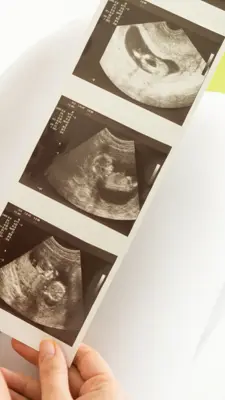

This week we're celebrating the sonography profession and the important role sonographers play in providing quality healthcare to Canadians. Sonographers help diagnose disease and injury, monitor health, and guide medical treatment.

Prenatal Screening Ontario (PSO) offers resources and point of care tools to support sonographers in performing high-quality nuchal translucency (NT) and crown-rump length (CRL) measurements.